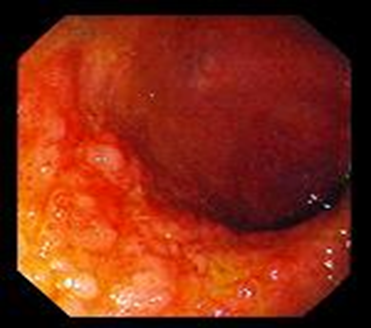

Klinika. Çox rəngarəngdir. Diareya və sorulma pozğunluqlarına görə çəki itkisi kardinal simptomdur. İshalsız gediş zamanı oynaq ağrıları (iltihablı və iltihabsız klinik gediş), yağlı və ya qanlı nəcis ifrazı, qarında spazmlar, köp, qızdırma, yorğunluq, dərinin tündləşməsi, iştahın azalması, limfa düyünlərinin böyüməsi, NB-ın selikli qişasında anomal sarı və ağ ləkələrin (endoskopik görünüş) əmələ gəlməsi kimi fərqli əlamətlər müşahidə olunur.

Endoskopik diaqnostika. Ezofaqoskopiya qida borusunun, videokameralı kapsul endoskopiyası nazik, fibrokolonoskopiya isə yoğun bağırsağın selikli qişasının üzvi dəyişikliklərini müəyyən etməyə, şübhəli sahələrdən biopsiya materialı götürməyə imkan verir. Biopsiya materialının bakterioloji müayinəsində Т. Whippeli bakteriyaları ilə infeksiyalaşmış toxumaların aşkar edilməsi diaqnozun verifikasiyasında həlledici rol oynayır.